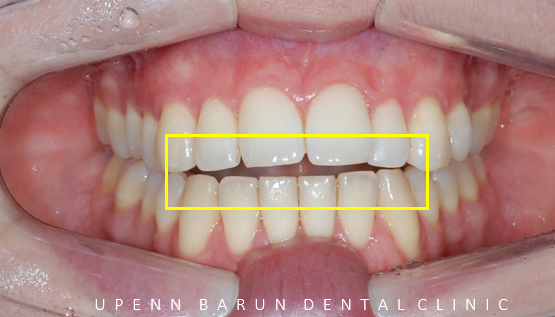

잠실인비절라인 개방교합 교정 후의 사진을 잠시 감상해보시면

전과 다르게 윗니 아랫니 사이의 공간이 닫히면서 개방교합이 완벽하게 해결되었습니다^^

뻐드러지고 삐뚤빼뚤했던 앞니들도 인비절라인교정을 통해 예쁘게 가지런해진 것을 볼수 있습니다.